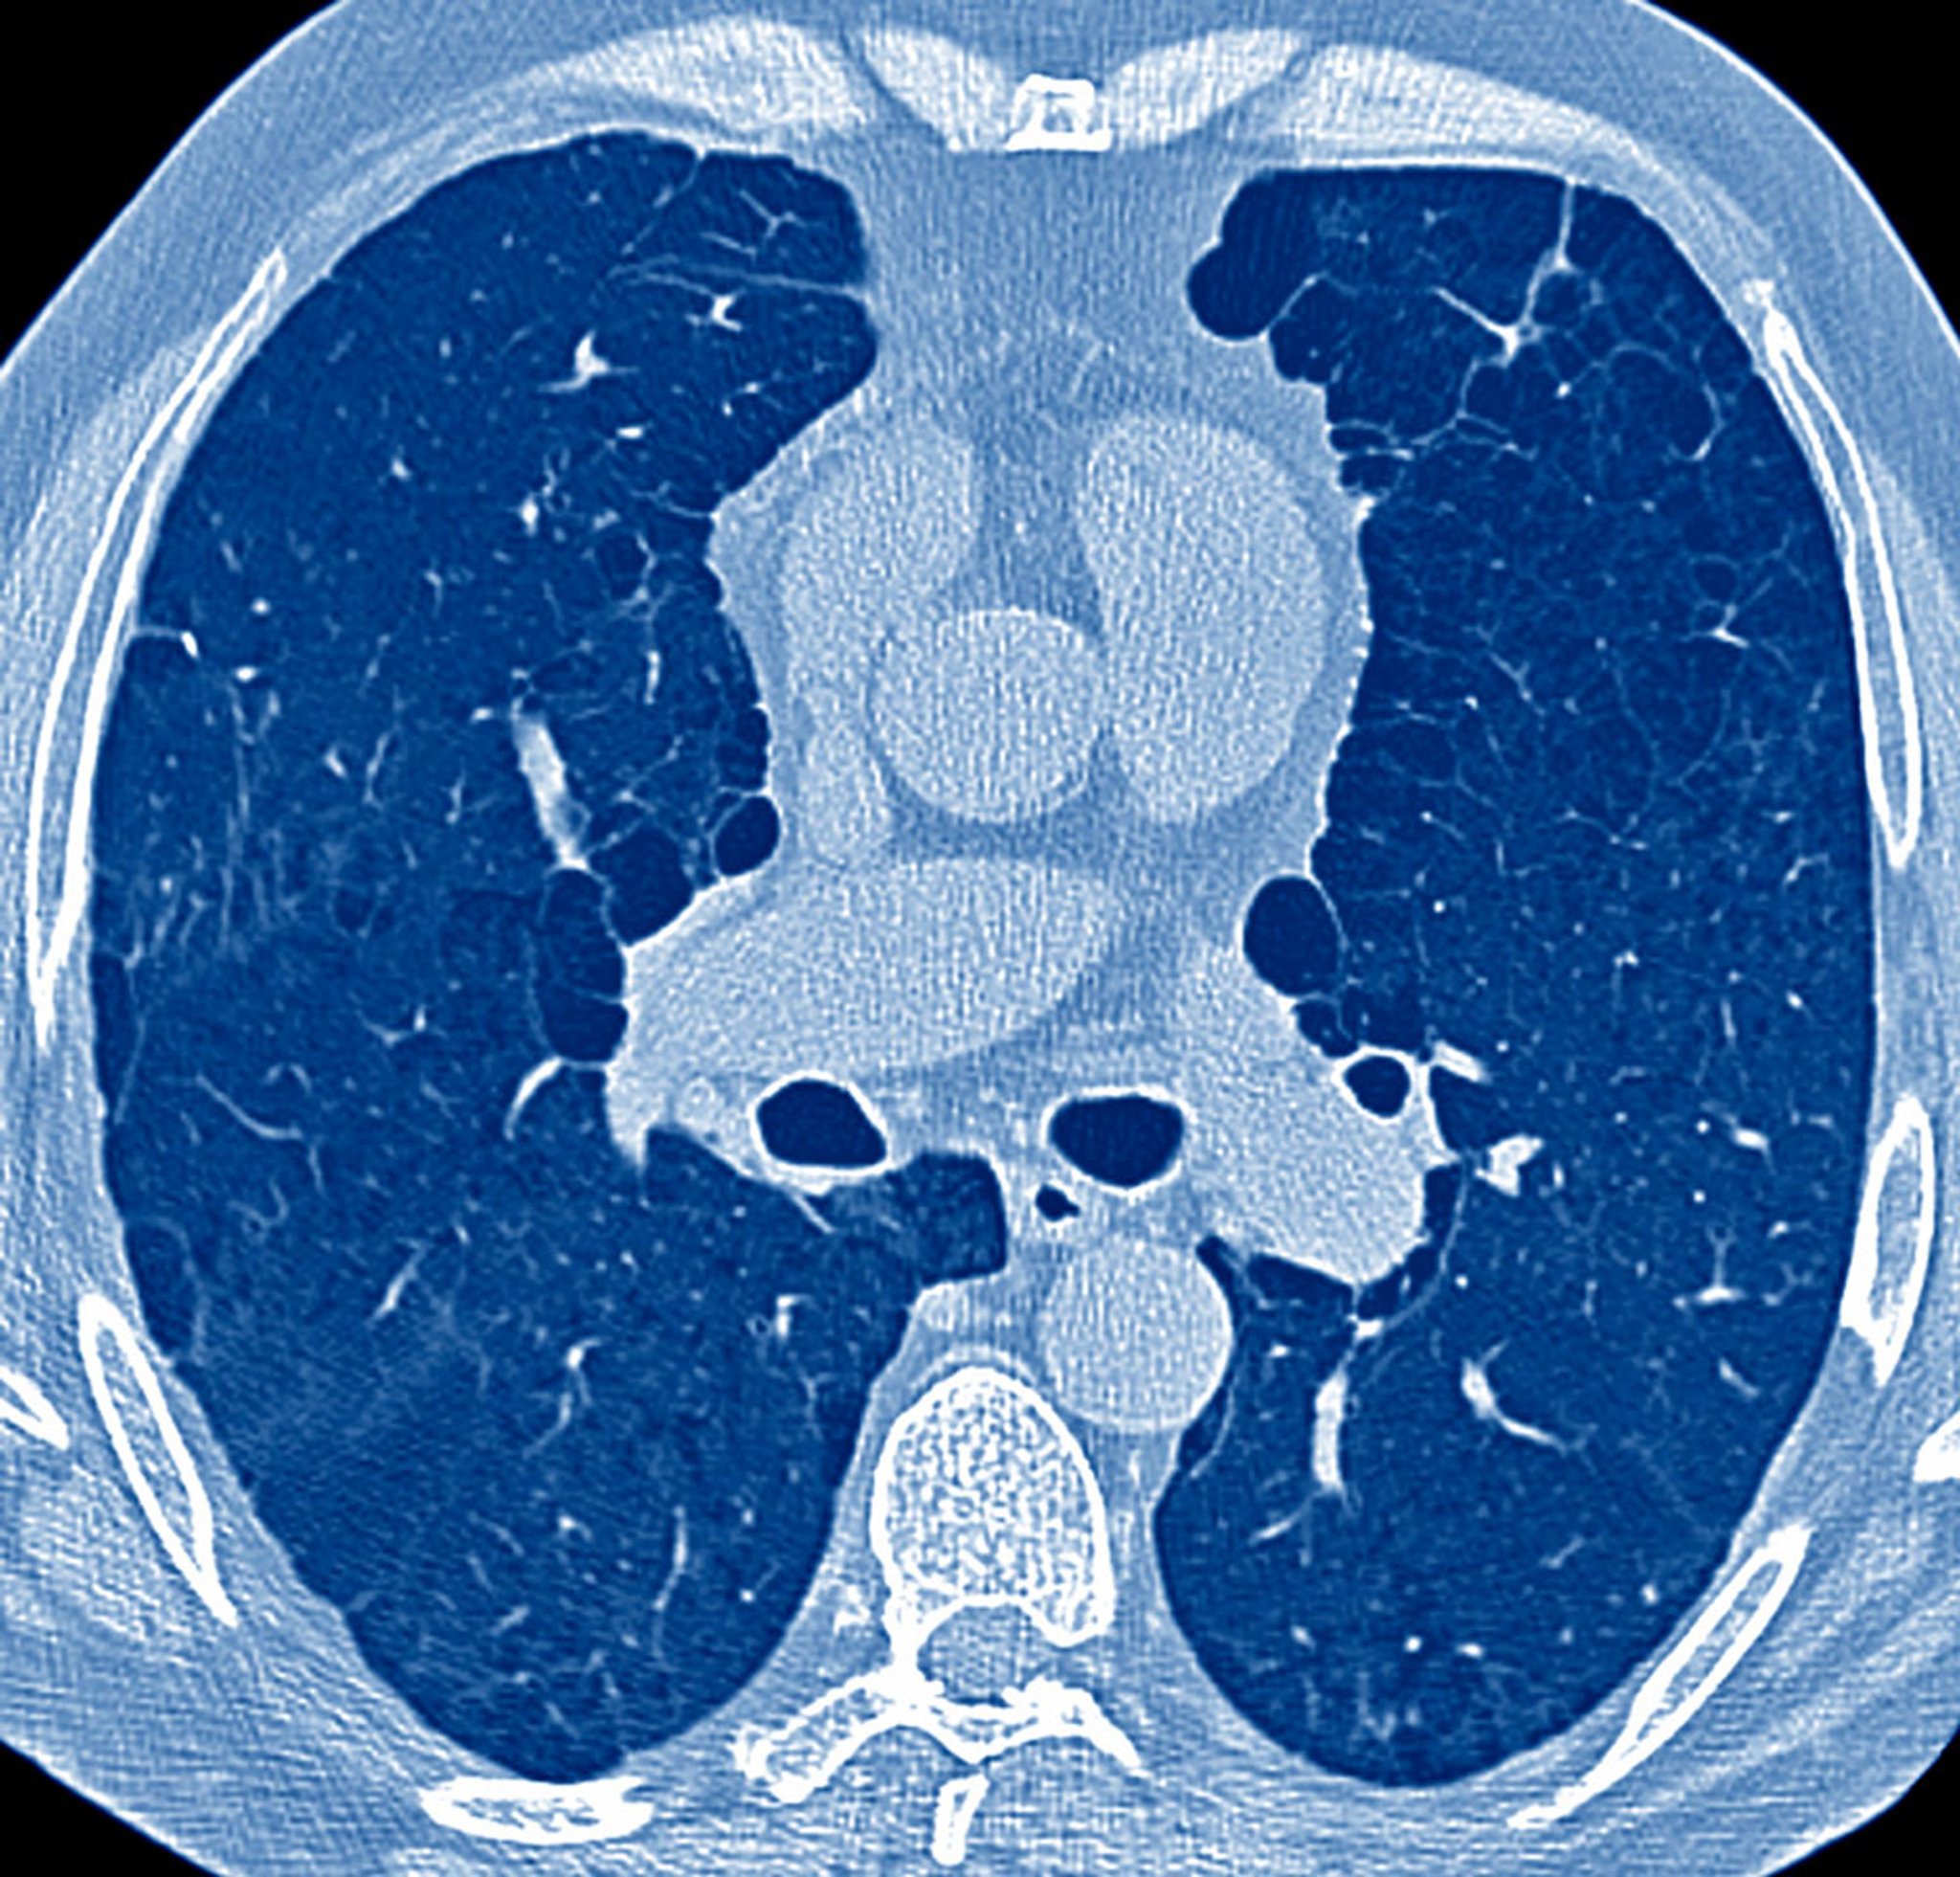

Increased Anterior-Posterior (AP) Diameter in Emphysema

This image shows markedly increased AP diameter with emphysematous changes in a CT scan of a patient who smokes. A barrel chest would be noted on physical examination.